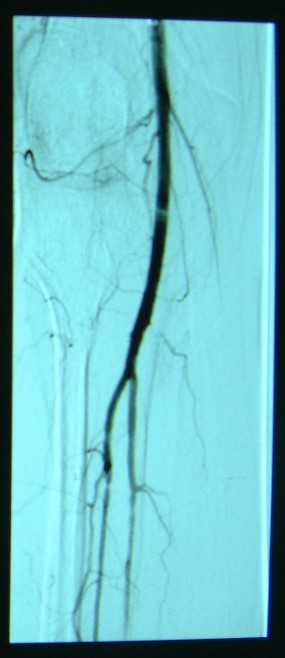

急性下肢動(dòng)脈缺血

治療前

治療后